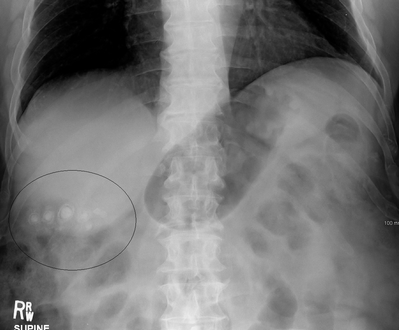

الحصوات المختلطة (الحصوة المصبغة البنية) تحتوي عادةً على 20-80٪ كوليسترول (أو 30-70٪، وفقًا لنظام التصنيف الياباني).[35] المكونات الشائعة الأخرى للحصوات المختلطة هي كربونات الكالسيوم، پالميتات الفوسفات، البيليروبين وغيرها من الأصباغ الصفراوية (بيليروبينات الكالسيوم، پالميتات الكالسيوم وإستيرات الكالسيوم). بسبب محتواها من الكالسيوم، فهي غالبًا مرئية إشعاعيًا. تنشأ عادة بشكل ثانوي نتيجة لعدوى القناة الصفراوية مما يؤدي إلى إطلاق بيتا-جلوكورونيداز (عن طريق خلايا الكبد المصابة والبكتيريا) الذي يتحلل البيليروبين جلوكورونيدات البيليروبين ويزيد من كمية البيليروبين غير المقترن في الصفراء. ما بين 4% إلى 20% من الحصوات هي حصوات مختلطة.[3]

صور طبقية محوسبة لحصوات المرارة.